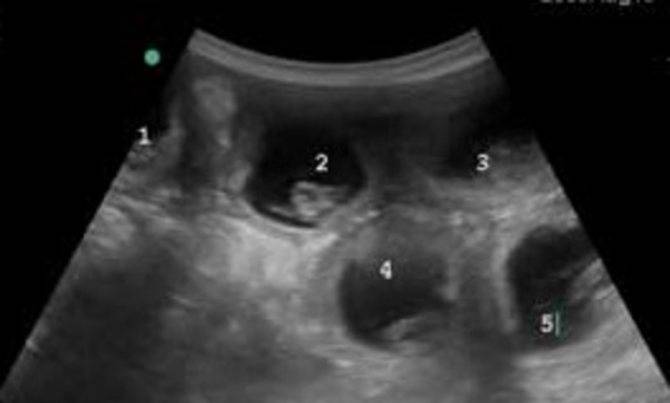

УЗИ (ультразвуковая сонография)

Считается одним из самых информативных методов, с помощью которого можно определить беременность кошки. На местах для потенциального контакта с ультразвуковым датчиком следует выстричь шерсть (с двух сторон от белой линии живота).

В зависимости от мощности аппарата внутри можно увидеть котят, зарегистрировать их сердцебиение. Через 20 дней после предполагаемой вязки можно обнаружить плоды, а через 28 – наличие двигательных рефлексов, возможные пороки развития, их жизнеспособность. Ранее проводить УЗИ бессмысленно.